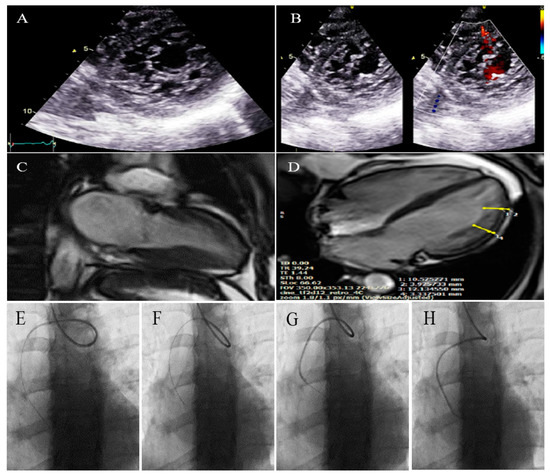

2.3. Case #3. NCLV with Aortic Dilation Complicated by Coronary Embolism

A 37-year-old gentleman with no history of cardiac disease and major CVD risk factors presented with acute retrosternal pain with radiation in both shoulders since 3 h prior to admission to the emergency department, accompanied by profound cold sweating and nausea, though there was no vomiting. On arrival, the ECG showed ST-segment elevation in the inferolateral leads, and diagnostic coronary angiography revealed a filling defect in the second obtuse marginal branch, in favor of occlusion by a fresh thrombus. He spent his hospital course uneventfully with response to anticoagulation plus dual antiplatelet therapy for 2 weeks (opened occlusion on the second angiography) and was discharged after 3 days in stable condition. Because of the possibility of the cardiac source of embolization, TTE and TEE were performed, which revealed NCLV with normal left ventricular ejection fraction (LVEF = 55%) and no obvious thrombus, in addition to mild aortic dilation (ascending aorta diameter = 42 mm; indexed = 22 mm). STE showed reduced global longitudinal strain (GLS = −11%). Moreover, CMR confirmed the diagnosis of NCLV (Figure 3). A genetic study showed two heterozygous mutations in the SCNIB and ALPK3 genes. The family screening was performed, and his mother had an undiagnosed isolated NCLV with the same genetic results, as well. The patient was prescribed warfarin and was symptom free at the follow-up visit.

Figure 3.

Two-dimensional transthoracic echocardiographic views of case #3. (A); Left ventricular apical SAX view, illustrating hypertrabeculated apical portions in addition to deep intertrabecular recesses. (B); Color Doppler echocardiography, showing evidence of direct blood flow from the ventricular cavity into deep intertrabecular recesses. (C); Dilated aortic proximal ascending aorta. (D); Speckle tracking echocardiographic findings, compatible with myocardial performance impairment of all segments with GLS = −14.3%. (E,F); Coronary angiography showing on arrival and 2-week post-treatment results. (G); Cardiac magnetic resonance imaging, illustrating prominent non-compaction in left ventricular apical and lateral wall.